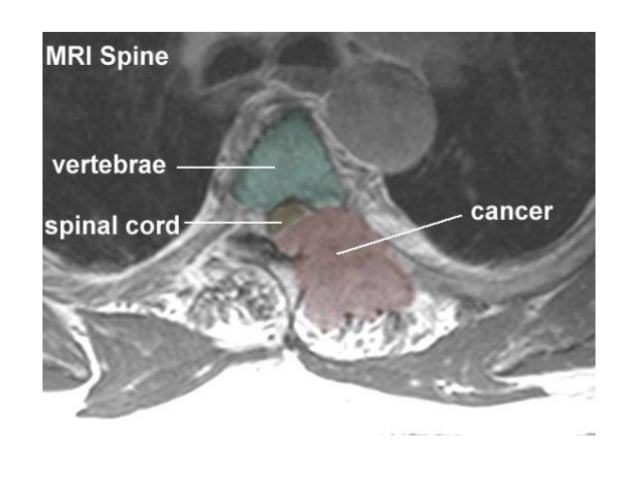

Compression of the spinal cord is due

predominantly to extradural metastases

(95%) and usually results from tumor

involvem...

MRI